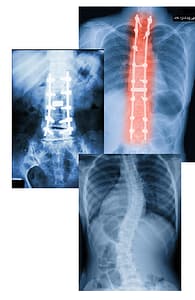

Pain Pump Therapy can be beneficial to people with: degenerative disc disease, neuropathy, sciatica, headaches from cervical pain, scoliosis, chronic pelvic and abdominal pain, radiculopathy, chronic back and neck pain, or have had failed back surgeries.

The intrathecal pain pump system consists of a pump and catheter, which are surgically placed under the skin. The pump is a round device, about the size of small tuna can, that stores and delivers pain medication, and it is placed in the abdomen, thigh, or buttocks. The catheter, a thin flexible tube, is inserted into the spine and connected to the pump. The pump sends the medication through the catheter to the spinal area. Pumps are refilled in office every 2-4 months when the pump is empty.

The pump releases prescribed amounts of pain medication through the catheter directly to the fluid around the spinal cord, which is called the intrathecal space.